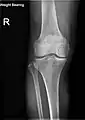

Fractures

Radiography to examine possible fractures after a knee injury

Knee fractures are rare but do occur, especially as a result of a road accident. Knee fractures include a patella fracture, and a type of avulsion fracture called a Segond fracture. There is usually immediate pain and swelling, and a difficulty or inability to stand on the leg. The muscles go into spasm and even the slightest movements are painful. X-rays can easily confirm the injury and surgery will depend on the degree of displacement and type of fracture.

X-ray